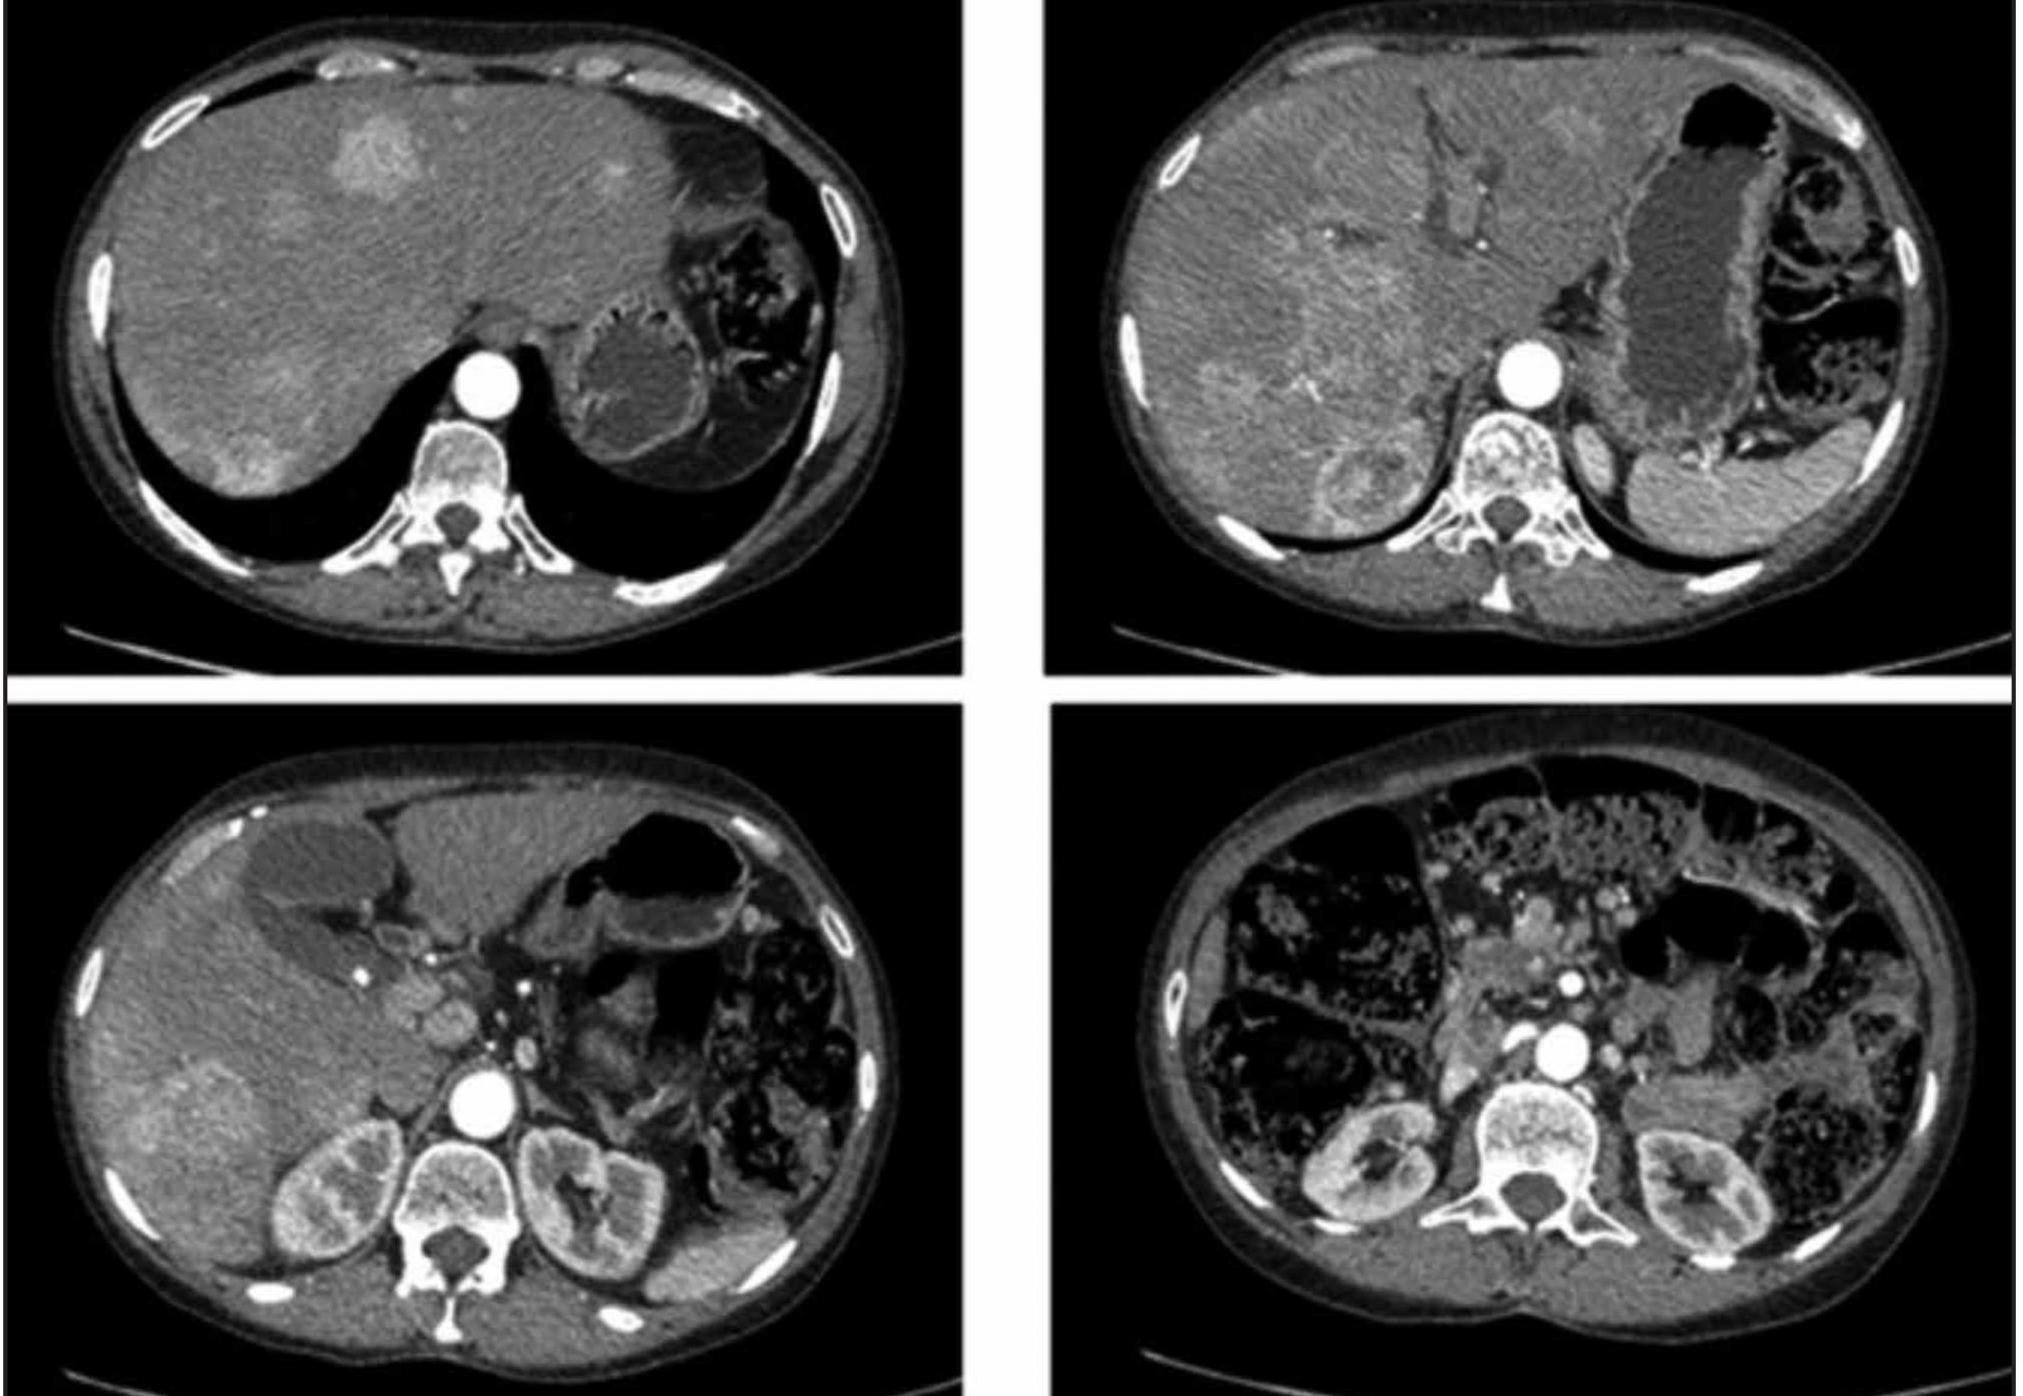

Pancreatic neuroendocrine tumors are cancer cells that developed from hormone-making cells islet cells in the pancreas. Neuroendocrine tumours of the pancreas show peak contrast enhancement in the early arterial phase 25-35 secs rather than in late arterial phase 35-45 secs which is normally used for. However in some cases a.